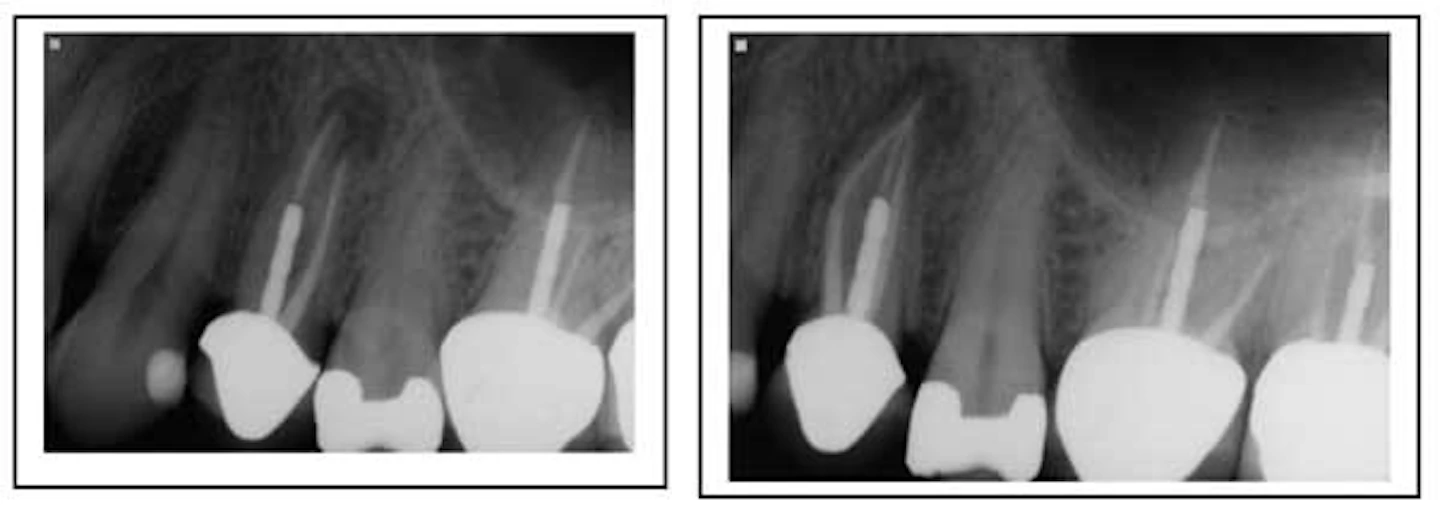

Nonsurgical Root Canal Retreatment Pocket Dentistry. On top of it, your insurance may. How much does root canal treatment cost? Find about affordable root canal treatment(rct) abroad in mexico, costa rica, india, colombia, vietnam.compare cost, precautions, best locations & more. | we also explain how prices for treatment typically vary with retreatment cases, or cases where an endodontist (root canal specialist) performs the work. Root canal treatment is scary as it is, and the prices quoted on the subject can spook you even more. This doesn't include additional procedures, which might turn out to be. Root canal therapy involves the soft inner core of a tooth, called the pulp. Another factor in the cost of root canals is how severe the cavity is and what needs to be done to repair the infected tooth. An rct can cost up to $2,100. Does anyone know what the average cost is for a root canal retreatment at an endodontist (i live in ontario, canada)?

Nonsurgical Root Canal Retreatment Pocket Dentistry , Retreatment Is A Bit More.